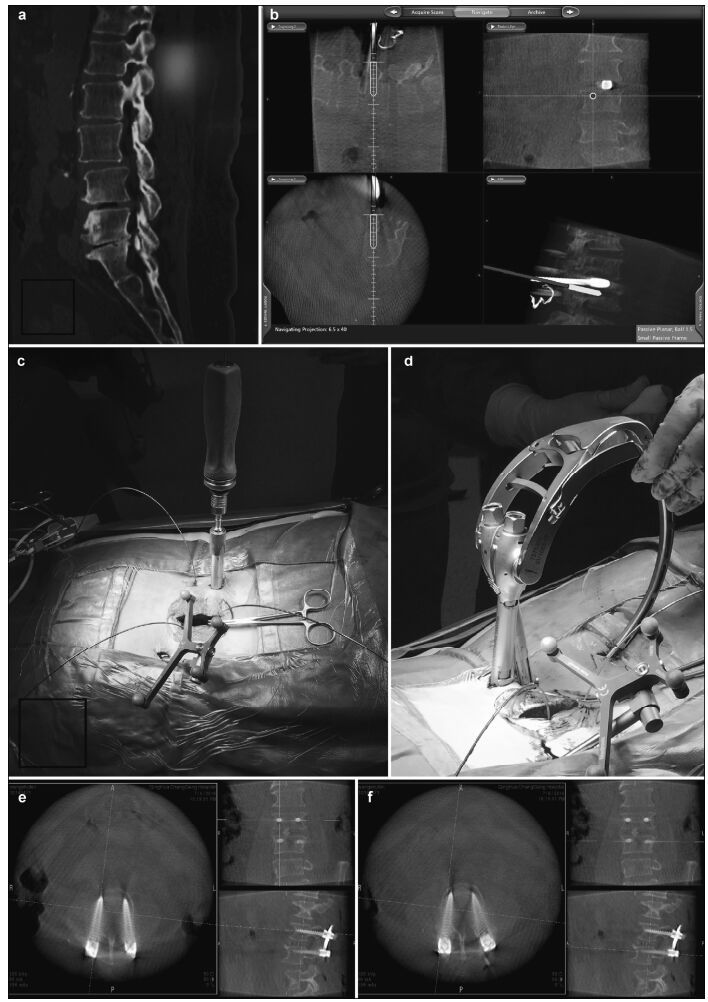

| Figure 5 Preoperative, intraoperative, and postoperative images of patients in the percutaneous minimally invasive pedicle internal fixation group. (a) Lumbosacral vertebral computed tomography shows L3 vertebral spondylolisthesis, L3-4 and L4-5 spinal stenosis, intervertebral disc degeneration, and corresponding intervertebral space narrowing. (b) Intraoperative L4 right pedicle screw implantation is performed under navigation. The direction, angle, and depth of screw entry can be seen in real-time, according to the navigation plan. (c, d) Intraoperative screw implantation and bar threading are performed under navigation. (e, f) After screw implantation, O-arm three-dimensional anteroposterior and lateral scans show that the screw is well positioned. |

For the thoracic/lumbar/sacral pedicle internal fixation group, 148 pedicle screws were implanted under navigational guidance. Intraoperative O-arm 2D lateral scans did not show screw position deviations, but the 3D scans found 148 Richter grade Ⅰ screws (0 screws penetrating the pedicle) and 4 grade Ⅱ screws that had deviated to the lateral pedicle (Figures 2-5).Intraoperative O-arm 3D scans were repeated for confirmation. Secondary correction was performed under navigational assistance, yielding a final accuracy of 97.3% (144/148).